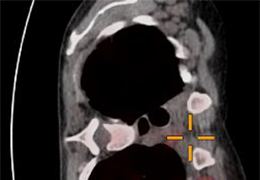

Designed mainly for CT and MR DICOM modalities.

Multi-planar slicing.

Oblique slicing.

Side-by-side comparative assessment for pre- and post-operative scans.